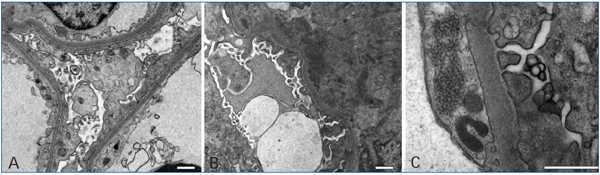

The classification of lupus nephritis was revised by the ISN/RPS in 2003. The increasingly recognized phenomenon of apparent minimal change disease (MCD) in the context of systemic lupus erythematosus (SLE), is not accepted in the above classification and is associated to a recent new pathological entity called lupus podocitopathy.1 A 32-year-old caucasian woman presented with arthralgia and swelling of the face, hands, and legs. Physical exam revealed pretibial edema and a patch of skin thickening on the left flank, consistent with morphea. Blood presure was 130/70mmHg; proteinuria 4.5g/dl; serum creatinine 0.9mg/dl; and albumin 2 g/dl. Urinalysis revealed fat casts. Serology was negative for hepatitis B, C, HIV-1 and HIV-2. ANA titer was 1/1300, C3 70mg/dl and anti ds-DNA was elevated. There was no history of nonsteroidal anti-inflammatory drug use in the patient. A diagnosis of SLE was made. Sections from the needle renal biopsy showed cortex with 10 normocellular glomeruli with mild mesangial hypercellularity and mesangial matrix increased. There were no evident tubular, interstitial, and vascular lesions (Figure 1 A). Immunofluorescence microscopy revealed mesangial granular deposition of IgG (2+) (Figure 1 B), IgA (1+), IgM (1+), C3 (2+) (Figure 1 C) and C1q (3+) (Figure 1 D). Ultrastructural analysis showed diffuse effacement (~80%) of the epithelial cell food processes and vacuoles (Figure 2 A). Moreover few electron-dense deposits were noted in mildly expanded mesangium (Figure 2 B). Subepithelial or subendothelial deposits were not observed in the biopsy. Numerous tubulorreticular inclusions within endothelial cells of glomerular capillary were also seen (Figure 2 C). A diagnosis of lupus podocytopathy and lupus nephritis Class I (ISN/RPS) was made. Of particular interest is the podocyte involvement in different types of lupus glomerulonephritis. For example, patients with non-nephrotic proteinuria and lupus nephritis Class I and II (ISN-RPS) have not revealed significant evidence of effacement of the foot processes. Nevertheless, some adult and children show minimal or proliferative mesangial lupus nephritis and nephrotic proteinuria without peripheral immune complex, exhibiting extensive podocyte effacement, consistent with lupus podocytopathy1. It is difficult to propose an exact pathogenic mechanism for this lesion given that immune deposits are no detected in glomerular basement membrane, even though it has been hypothesized different mechanisms. Abnormal release of IL-13 from aberrant T cell2, crosstalk between renal dendritic cells and Th cells3 may directly damage to podocytes. Our patient was treated with high-dose prednisone. Six month later she remained normotensive, had no edema, with normal serum creatinine and decreased urinary protein excretion (0,5g/d). In agreement with this result Kraft et al1 have shown a significant reduction in proteinuria at last follow-up. Therefore, the podocytopathy in the SLE context responded to oral corticosteroids, remarking the important therapeutic implications of the diagnosis of this particular entity. In summary, lupus podocytopathy has become an intersting point both clinical discussion and futures investigations about the role of podocyte and it should be added to the classification of lupus nephritis.

Figure 1. Light microscopy and immunofluorescence findings